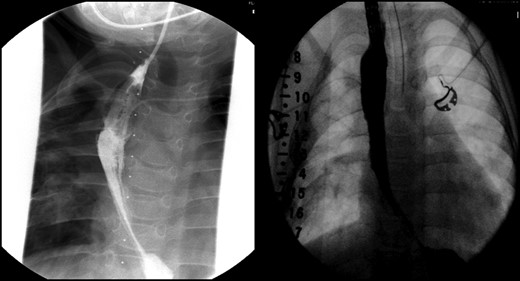

Daily tightening of her traction sutures was performed until the distal esophageal segment reached the chest wall (Fig. 2). The cervical esophagostomy was also sequentially lengthened and eventually internalized. Three traction suture revisions and two proximal esophageal lengthening operations were performed before esophageal continuity was re-established (46 days). Two subsequent anastomotic leaks occurred; 1 anastomotic leak was repaired surgically, whereas one subsequent leak was managed nonoperatively with a chest tube. Five dilations and, one, 13-day retrievable stent placement were needed for anastomotic narrowing. A comparative postoperative esophagram and intraoperative esophagram illustrated neither a stricture nor an anastomotic leak (Fig. 3). Total hospitalization was 112 days.

Fluoroscopic examination illustrating incremental ‘growth’ of the distal (lower) esophageal segment while the patient was undergoing external traction (Foker Stage 1). The contrast was injected through her existing gastrostomy tube. The metal dot refers to her esophagostomy; thus, can measure the distance between the ends of her esophageal segments.